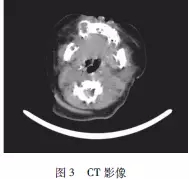

患者,男,3個月。2周前于右上牙區(qū)發(fā)現(xiàn)紅豆大小腫物,考慮“馬牙”未予重視?,F(xiàn)發(fā)現(xiàn)腫物呈黃豆大,遂來我院就診。體查:右上唇至右眶下孔處隆起明顯(圖1),右上頜骨處有一半球形腫物,向頰側(cè)膨隆,約蠶豆大小,呈淺藍色,界清,表面無紅腫破潰,質(zhì)硬,不活動(圖2)。下頜下淋巴結(jié)未及腫大。外院CT示:右上頜骨占位,懷疑成釉細胞瘤”(圖3)。